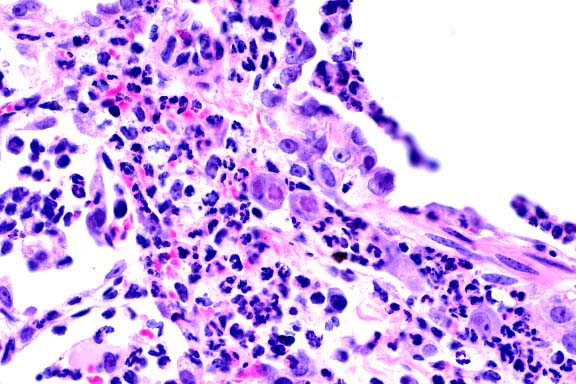

- Conference Note: Variably affecting the sections of

lung, there are multifocal to coalescing areas of atelectasis

and consolidation. Bronchioles are partially or completely filled

by numerous viable and degenerate neutrophils admixed with fewer

macrophages, necrotic respiratory epithelial cells, abundant

cellular debris, few bacilli, and mucin. There is occasional

segmental attenuation and loss of the bronchiolar epithelium.

Similar inflammatory cells partially or completely fill adjacent

alveoli.

- Several concurrent infectious agents complicate the histologic

lesions of the lung. The presence of bacilli in bronchioles and

bacterial culture results suggest that the bronchopneumonia was

primarily caused by infection with Bordetella bronchiseptica.

The interstitial pneumonia, with characteristic multinucleate

giant cells, was attributed to infection with SIVmac. Concurrent

infection with cytomegalovirus also contributed to the interstitial

pneumonia. These oppurtunistic pulmonary infections are common

in SIV/SHIV infected macaques.